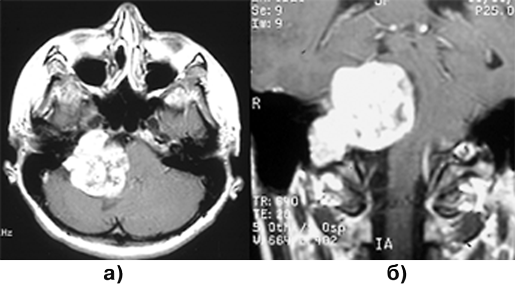

Особую проблему представляют опухоли в виде «песочных часов», чаще невриномы, которые по мере роста распространяются из интрадурального пространства через межпозвонковое отверстие паравертебрально (рис. 3). Такие опухоли удаляются в 2 этапа: вначале обычно удаляется интрадуральная часть опухоли, затем при боковом расширении обычного срединного доступа или из нового доступа (например трансторакального) — экстраспинальный узел новообразования. При этом для радикального удаления опухоли вместе с ней приходится резецировать проходящий через спинальное отверстие не только чувствительный, но и двигательный корешок.

Рисунок 3. Эксрамедуллярная интрадуральная опухоль в форме «песочных часов» (невринома) грудного отдела позвоночника (МРТ с контрастным усилением, Т–1 взвешенные изображения)

Диагностика основывается на данных МРТ (рис. 4), для оценки костных изменений обычно производятся спондиллограммы и КТ. Для принятия решения об оптимальной тактике лечения необходима верификация степени распространения онкологического процесса, включающая радиоизотопное сканирование костей скелета, рентгеновское (включая КТ) и/или УЗИ щитовидной железы, органов грудной клетки, брюшной полости, забрюшинного пространства и малого таза.

Рисунок 4. Метастаз аденокарциномы в 12 грудной позвонок, вызывающий компрессию дурального мешка. МРТ с контрастным усилением:

а — Т1-взвешенные изображения, сагиттальная проекция; б — Т2-взвешенные изображения, фронтальная проекция